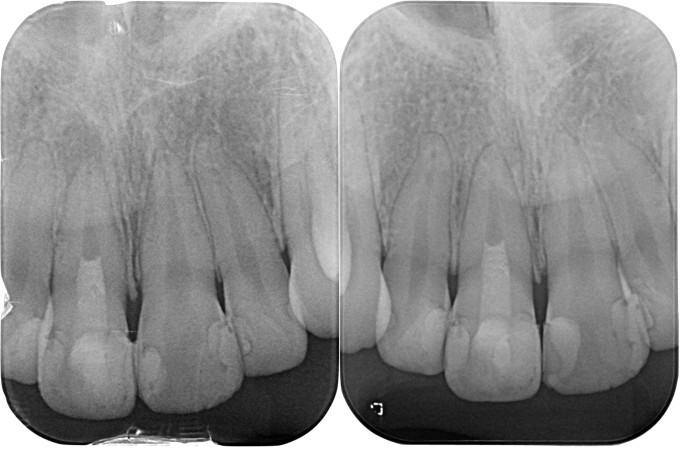

(図19)初診時のレントゲン所見

ほとんどが有髄歯であり無髄歯は左上1番と左下6番のみ左下6番は歯根破折しており抜歯を予定